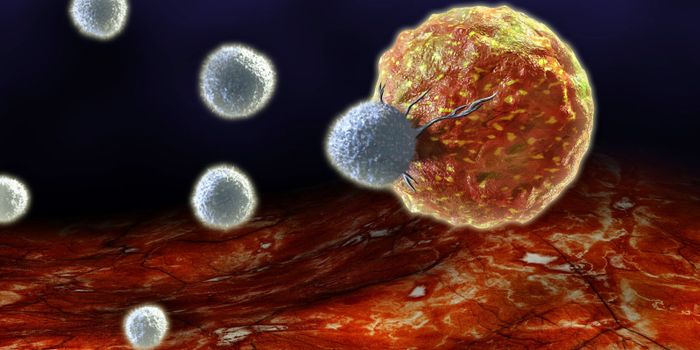

DEC 10, 2015ImmunologySuperior technology brings us novel images of cancer cells and lymphocytes this week, and now scientists can learn more ...

NOV 20, 2019ImmunologyManipulating the immune system’s population of natural killer cells could bolster therapies targeting cancer. A ne ...